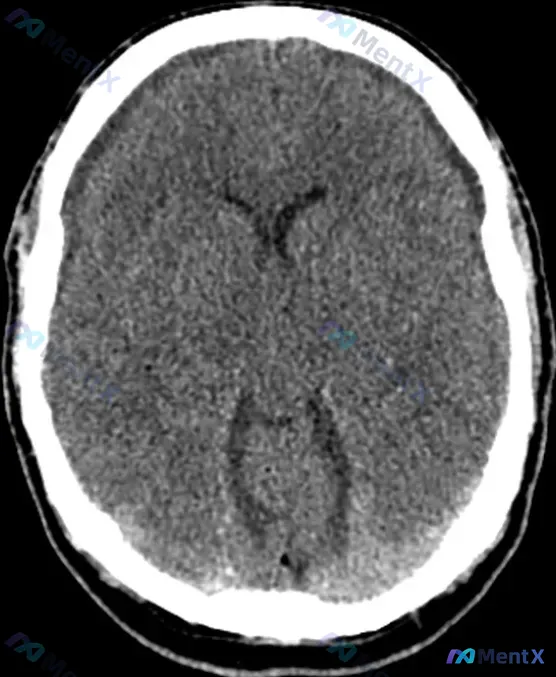

今天看到一份影像资料有点感慨——输入明确写了“Bifrontal hypoattenuating subdural collections(双侧额部低密度硬膜下积液)”,但原始影像分析结论却写着“颅内结构未见明显病理改变”。

- 影像核心发现:头部CT平扫横断面显示双侧额部硬膜下腔可见低密度影(接近脑脊液密度)。

- 其他影像信息:

- 脑实质灰白质分界清,未见明确急性出血/梗死灶;

- 中线结构居中,脑室系统大小形态对称;

- 侧脑室三角区可见脉络丛生理性钙化;

- 无明显占位效应(脑沟无普遍增宽或局部受压变窄)。